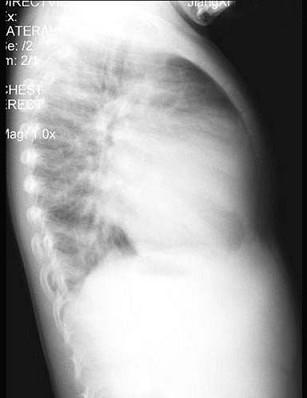

问题 男性,1岁零8个月,生长发育差,易患呼吸道感染,心悸气促,行心脏正、侧位片检查如图所示,正确的描述和结论是 ( )

选项 A、房间隔缺损 B、室间隔缺损 C、肺纹理增多 D、侧位示心前间隙变窄,心后食管前三角间隙消失 E、正位示心影向两侧扩大,心尖左移

答案 BCDE